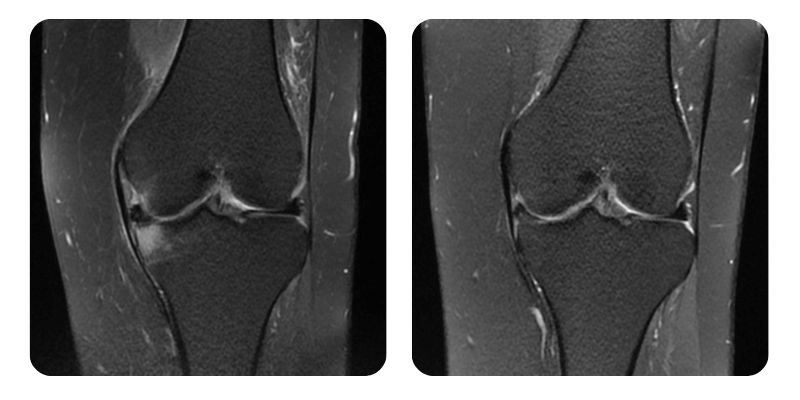

Prima

Dopo

K.D., 32 anni - Edema del condilo femorale mediale sinistro e del piatto tibiale ipsilaterale

Diagnosi: Edema del condilo femorale mediale sinistro e del piatto tibiale ipsilaterale.

Evoluzione: Alla rivalutazione la paziente riferisce una quasi completa scomparsa del dolore, presente solo alla flessione del ginocchio. In precedenza il dolore era 8/10, attualmente 1/10. La mobilita e nettamente migliorata; prima della terapia la flessione era impossibile.

Prognosi: Molto buona. Mobilita significativamente aumentata, assenza di dolore, sensibilita periferica, funzione motoria e vascolarizzazione integre. Guarigione confermata radiologicamente e clinicamente per circa il 90%.